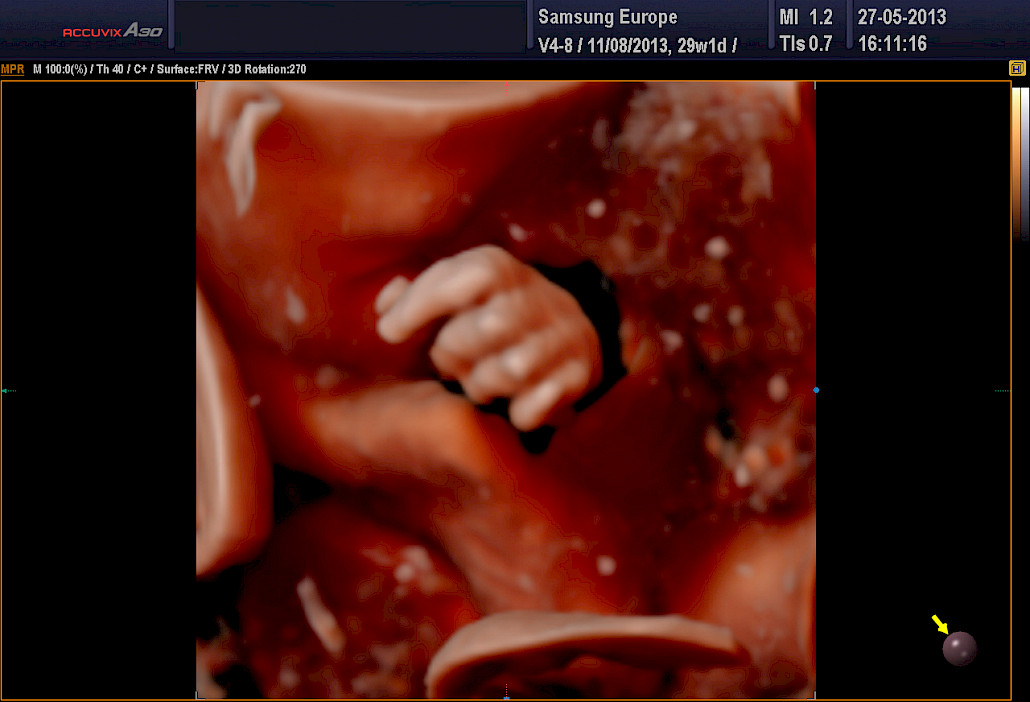

3D ja 4D-tekniikat soveltuvat erityisen hyvin sikiön kasvojen anatomian tutkimiseen. Tutkimuksessa poissuljetaan mahdollinen huulihalkio ja kasvojen profiilissa esiintyvät muut poikkeamat, kuten liian pieni leuka. Samalla selvitetään korvien anatomia ja niiden sijainti. Tekniikan avulla selvitetään raajojen asennot, sekä sormien ja varpaiden lukumäärä ja niiden liikkuvuus. Lisäksi tutkitaan koko selkärangan rakenne ja suljetaan pois poikkeamat, kuten puuttuvat lapa- tai olkaluut.

Kuva Femedan 4D-ultraäänitutkimuksesta